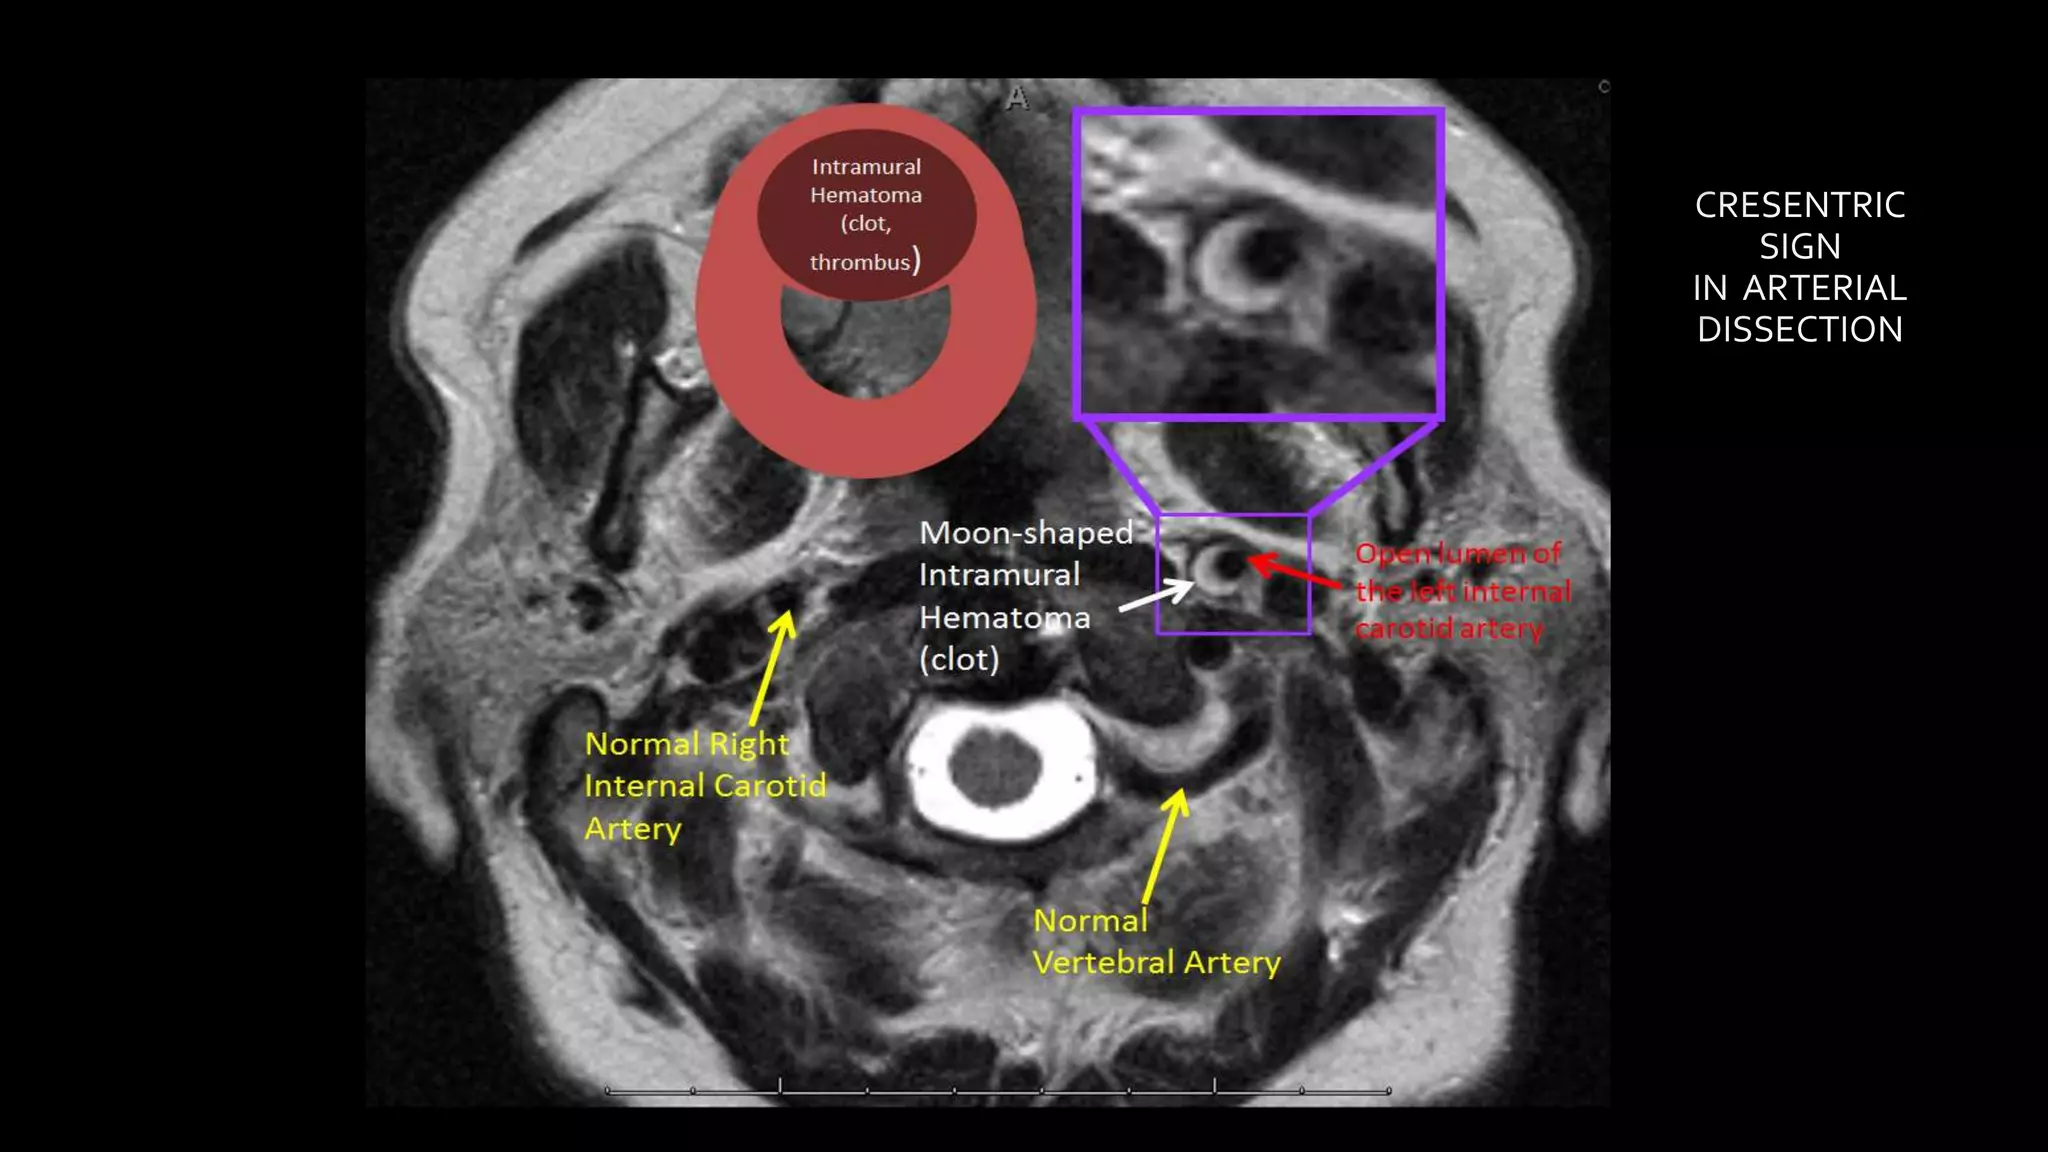

• #162 Here is an example of a young patient presenting with severe acute neck pain SHOWING left ICA dissection ON T2wi AS crescentric shaped hyperintense intramural hematoma causing expansion of the artery. However there is no narrowing of ICA lumen

• #163 Another example showing circumferential intramural hematoma seen bilaterally causing expansion of the bilateral ICA . There is narrowed lumen of the right ICA and open lumen of the left ICA